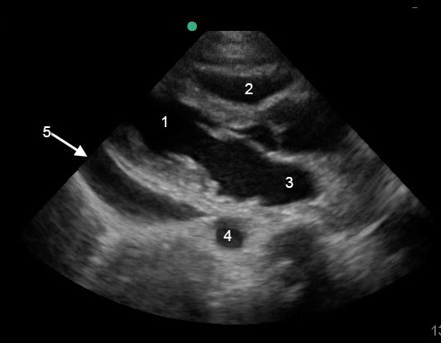

RUSH 泵图像

左心室 (LV)

右心室 (LV)

左心房 (LA)

降主动脉

心包液